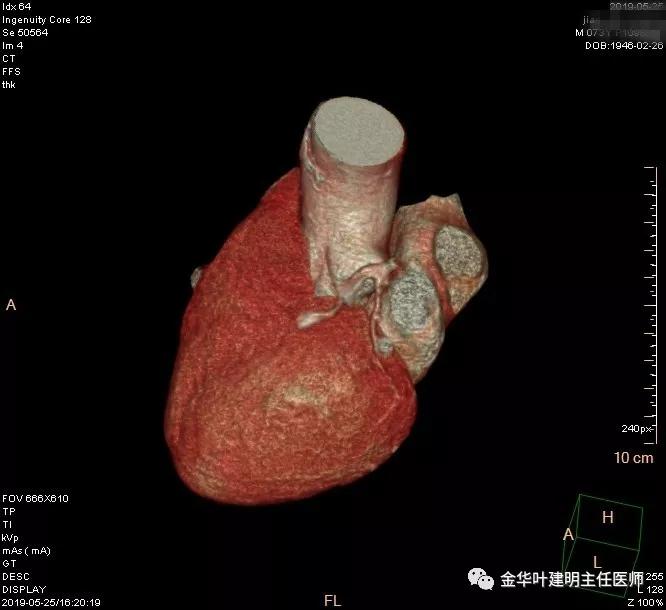

患者,男性,73岁,金华人。因“咳嗽咳痰伴胸闷2月,检查确诊左肺癌1周”入院。气管镜: 气管支气管内较多脓性分泌物,左肺上叶前段管腔新生物,局部活检、毛刷。气管镜病理:(左肺活检)鳞癌。阅胸部CT见左上叶开口处新生物,考虑需左上叶袖式切除及淋巴结清扫。具体CT表现如下:

术前检查冠脉CT示:左冠前降支近段多发钙化斑块伴管腔重度狭窄(约85%),建议DSA检查。但追问病史以往平时无胸痛或胸闷症状,运动试验提示可疑阳性(上斜型压低),活动后胸闷气闭症状不明显,既往否认高血压、糖尿病。所以经过心内科会诊讨论,认为还是可以进行手术。术前冠状动脉CT示: